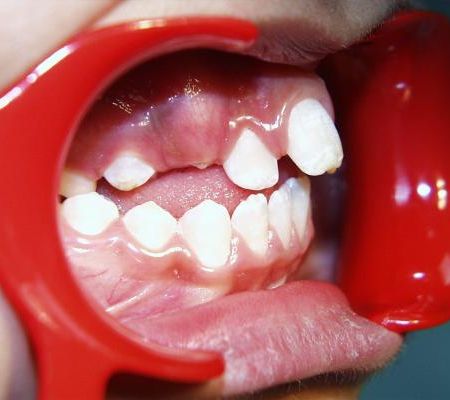

Beim nächsten Fallbeispiel war der Oberkiefer deutlich zu schmal im Verhältnis zum Unterkiefer, der Biß war frontoffen und die oberen Schneidezähne standen sehr unregelmäßig bei einer auffallenden Mittenverschiebung nach links.

Vor der Behandlung